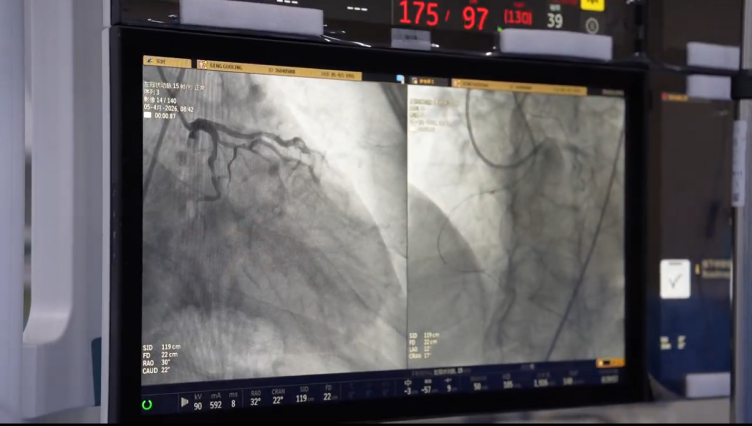

该患者因“胸闷3月、加重1天”入院,既往冠脉造影显示“三支病变”合并“右冠状动脉慢性闭塞”,且曾尝试介入治疗未能开通。此次手术面临三大难关:右冠开口先天畸形、长段闭塞伴严重钙化、逆向侧枝合并重度狭窄导致缺血风险极高。术中,导丝极易在严重钙化的血管内发生偏移,手术历时三个半小时,手术难度等级堪称“天花板级别”。

面对挑战,山东南郊医学研究院胡涛心血管病研究中心胡涛院长凭借深厚造诣,巧妙结合正向与逆向介入技术,灵活运用Knuckle导丝技术,最终突破重重解剖学阻碍,成功开通了闭塞已久的右冠状动脉。这一成功案例标志着济南南郊医院在复杂冠脉介入治疗领域已达到国内先进水平。